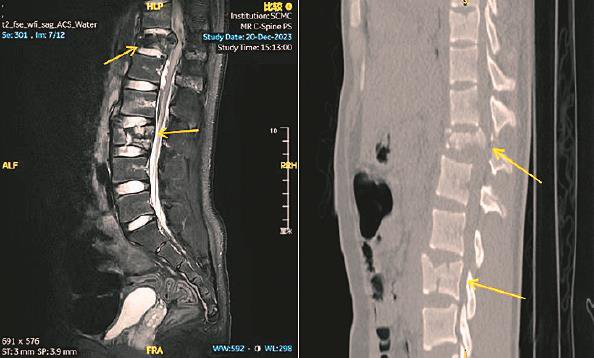

右上图:术前CT示胸腰椎多发爆裂性骨折伴移位

15岁的孟迪(化名)在夜间“梦游”时,不慎从6楼家中坠落,一小时后才被人发现。当时他虽意识清醒,但双下肢已无法站立,感觉麻痹。家属立即拨打120将孩子送至上海交通大学医学院附属上海儿童医学中心急诊。入院后,CT结果提示其胸、腰椎多发爆裂骨折,情况十分危急。